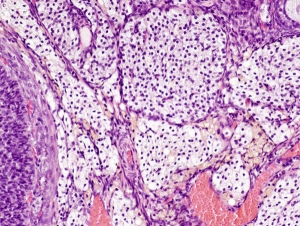

Roma, 29 marzo 2018 - Rivoluzione in arrivo in anatomia, con la scoperta di un nuovo organo, tra i più grandi del corpo umano: si chiama interstizio e si trova diffuso in tutto l'organismo, sotto la pelle e nei tessuti che rivestono l'apparato digerente, i polmoni, i vasi sanguigni e i muscoli. E' formato da cavità interconnesse piene di liquido e ...